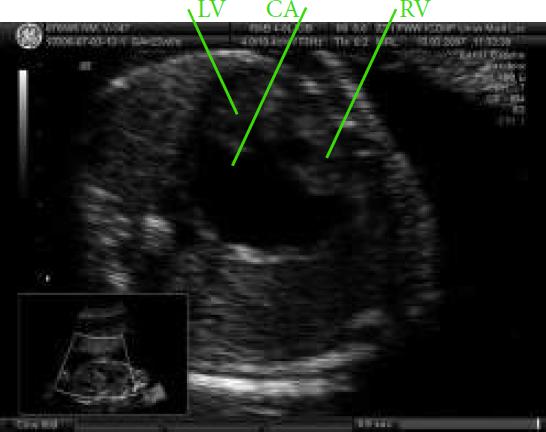

Fetal heart defect and complete heart block in a case of prenatal left isomerism, CA – common atrium, RV – right ventricle, LV – left ventricle.Ryc. 7. Obraz wady serca powikłanej blokiem całkowitym w przebiegu izomeryzmu lewostronego: CA wspólny przedsionek, RV – prawa komora, LV – lewa komora, PA.